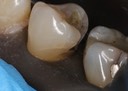

Joe Cha #18 prep